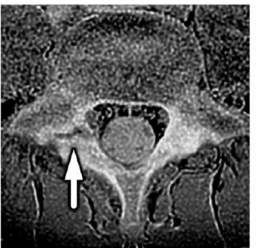

【画像:https://kyodonewsprwire.jp/img/202512030261-O4-1IWaCL03

図2: 腰椎分離症のMR画像(画像は腰椎の水平断面を示す。矢印は腰椎分離症の病態箇所である)